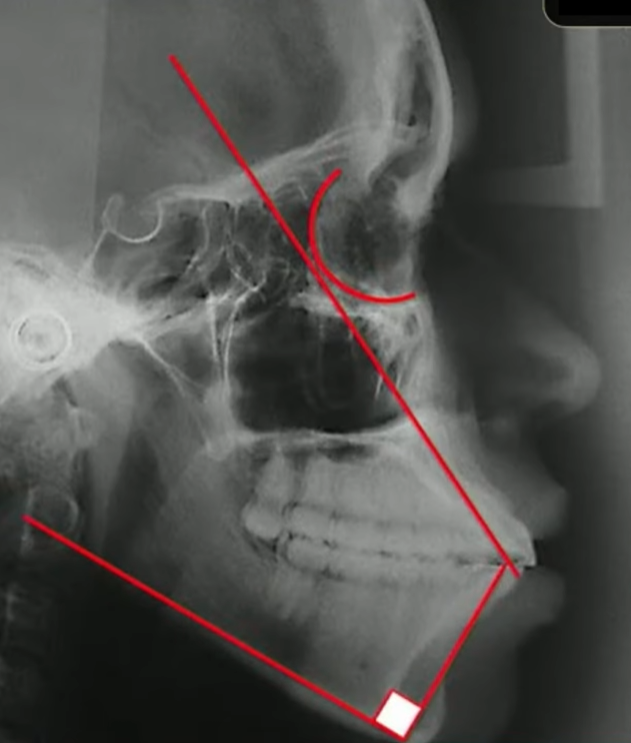

E aqui eu tiro a prova dos 9, eu tenho certeza absoluta que esse incisivo está vestibularizado porque eu tracei o longo eixo dele, ele passou muito atrás dessa órbita:

E eu também consigo traçar o meu incisivo inferior, medindo ele com a base mandibular:

Quando eu faço essa medida do incisivo inferior com a base mandibular, qual a minha intenção?

Eu quero saber também se esse incisivo inferior está mais ou menos com 90 graus em relação à base mandibular, nesse caso aqui eu tenho os incisivos bem vestibularizados.